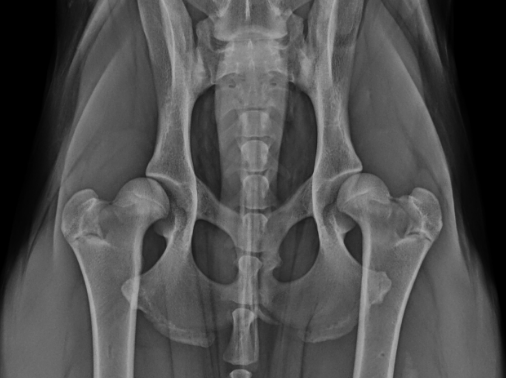

Back to Surgery Information Pet Owner Information Hip Dysplasia What is Hip Dysplasia? Hip dysplasia is laxity and incongruence of the “ball and socket” hip joint that results in joint inflammation, pain and the development of osteoarthritis. Hip dysplasia is...